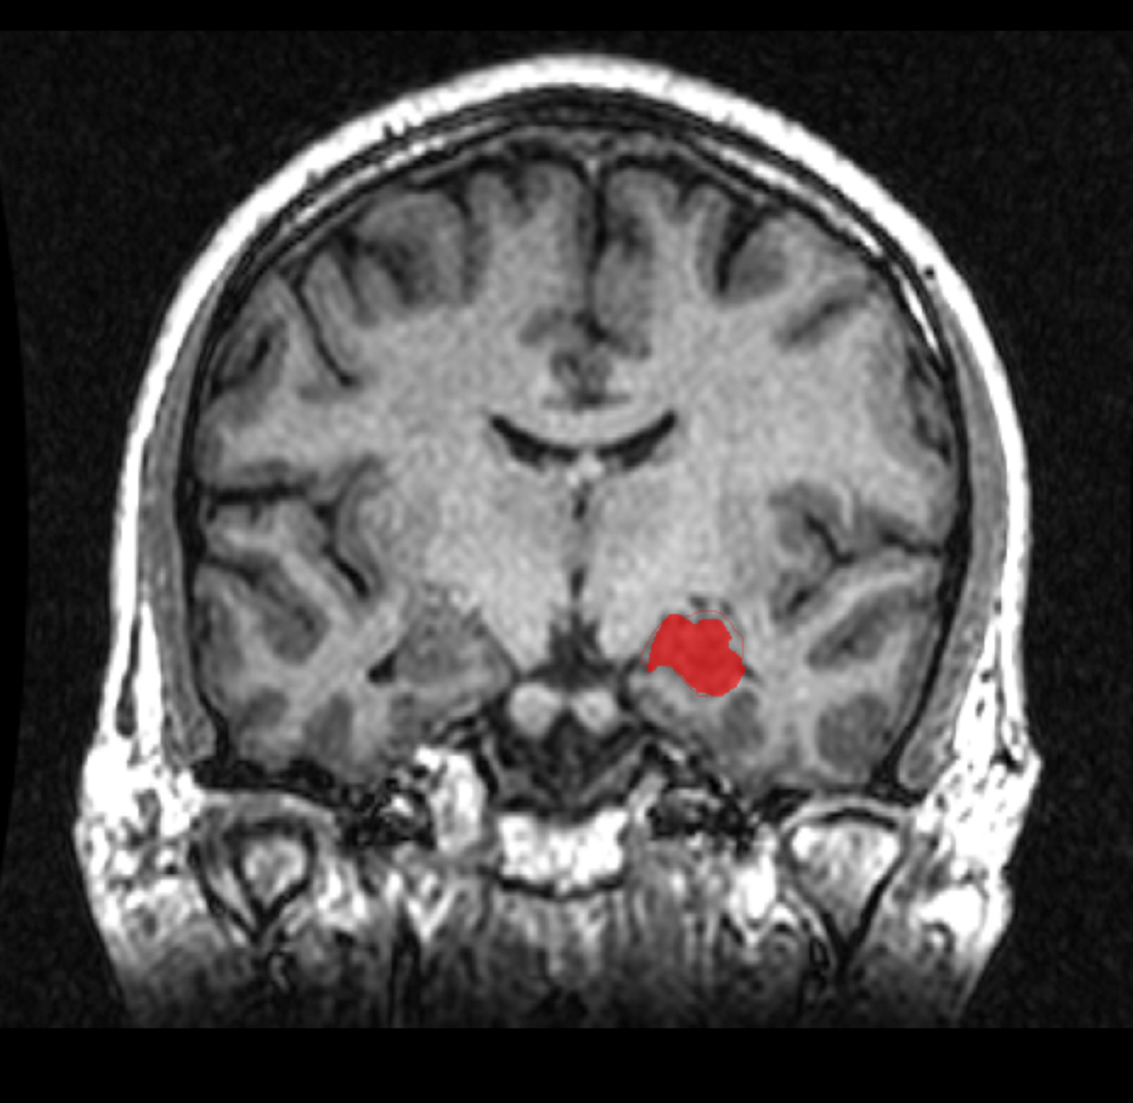

Imagen por resonancia magnética de un hipocampo (en rojo). Imagen: Amber Rieder/Jenna Traynor. Fuente: Wikipedia.

Una investigación de la Universidad Rosalind Franklin de Medicina y Ciencia (Illinois, EE.UU.) ha desmentido la creencia generalizada de que el hipocampo, una parte crucial del cerebro que consolida nuevos recuerdos y ayuda a conectar las emociones con los sentidos, es mayor en las mujeres que en los hombres.

Lise Eliot, profesora asociada de neurología en la Facultad de Medicina de la universidad, dirigió un equipo de estudiantes en un meta-análisis de volúmenes del hipocampo medidos con resonancia magnética, que no encontró ninguna diferencia significativa entre hombres y mujeres.

Los hipocampos se encuentran a ambos lados del cerebro, bajo la corteza cerebral. Los hallazgos del equipo desafían la afirmación habitual de que un hipocampo desproporcionadamente mayor explica la tendencia de las féminas hacia una mayor expresividad emocional, habilidades interpersonales más fuertes y una mejor memoria verbal.